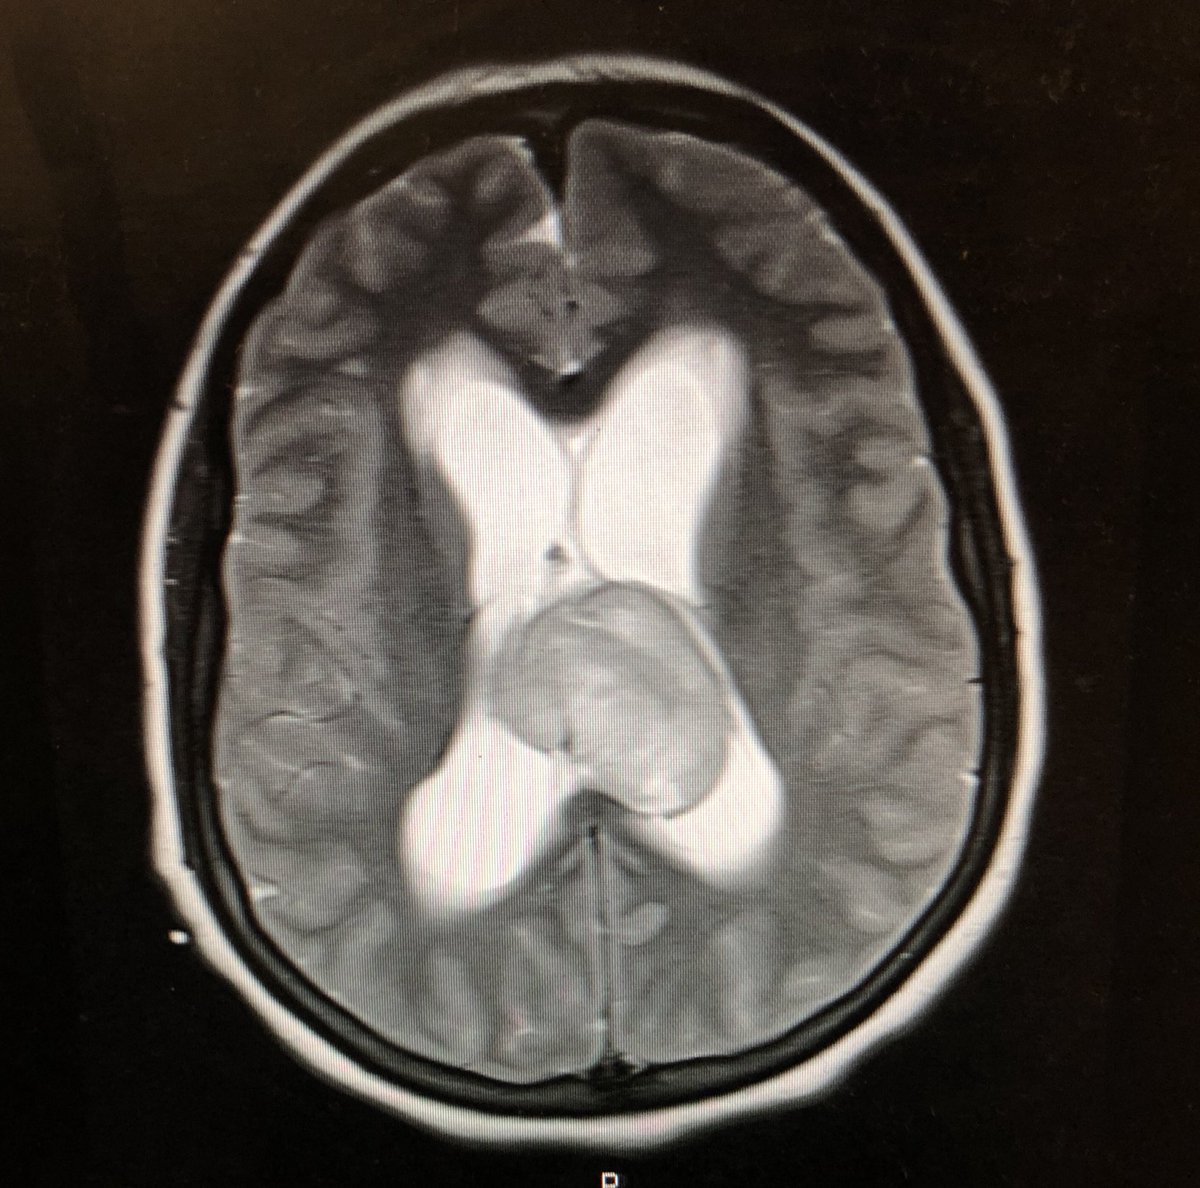

Fabulous to push the boundaries of #glioblastoma treatment with @johnboockvar @lenoxhill @NorthwellHealth and read about positive response of Daniel https://t.co/IK5nsuneIp using #EnGeneIC EDV tech.

We are currently enrolling #GBM patients for our EnGeneIC Dream Vector (EDVTM) nanocell-based technology, a new way of delivering chemotherapy drugs for the treatment of #braintumors. https://t.co/EUGTQusUoq @LenoxNeurosurg @NorthwellHealth 4 info please contact @ShereseFralin

Congrats to our @LenoxNeurosurg #braintumor research team for treating our first patient in @EnGeneIC EDV trial for #gbm @BrainCancerCure